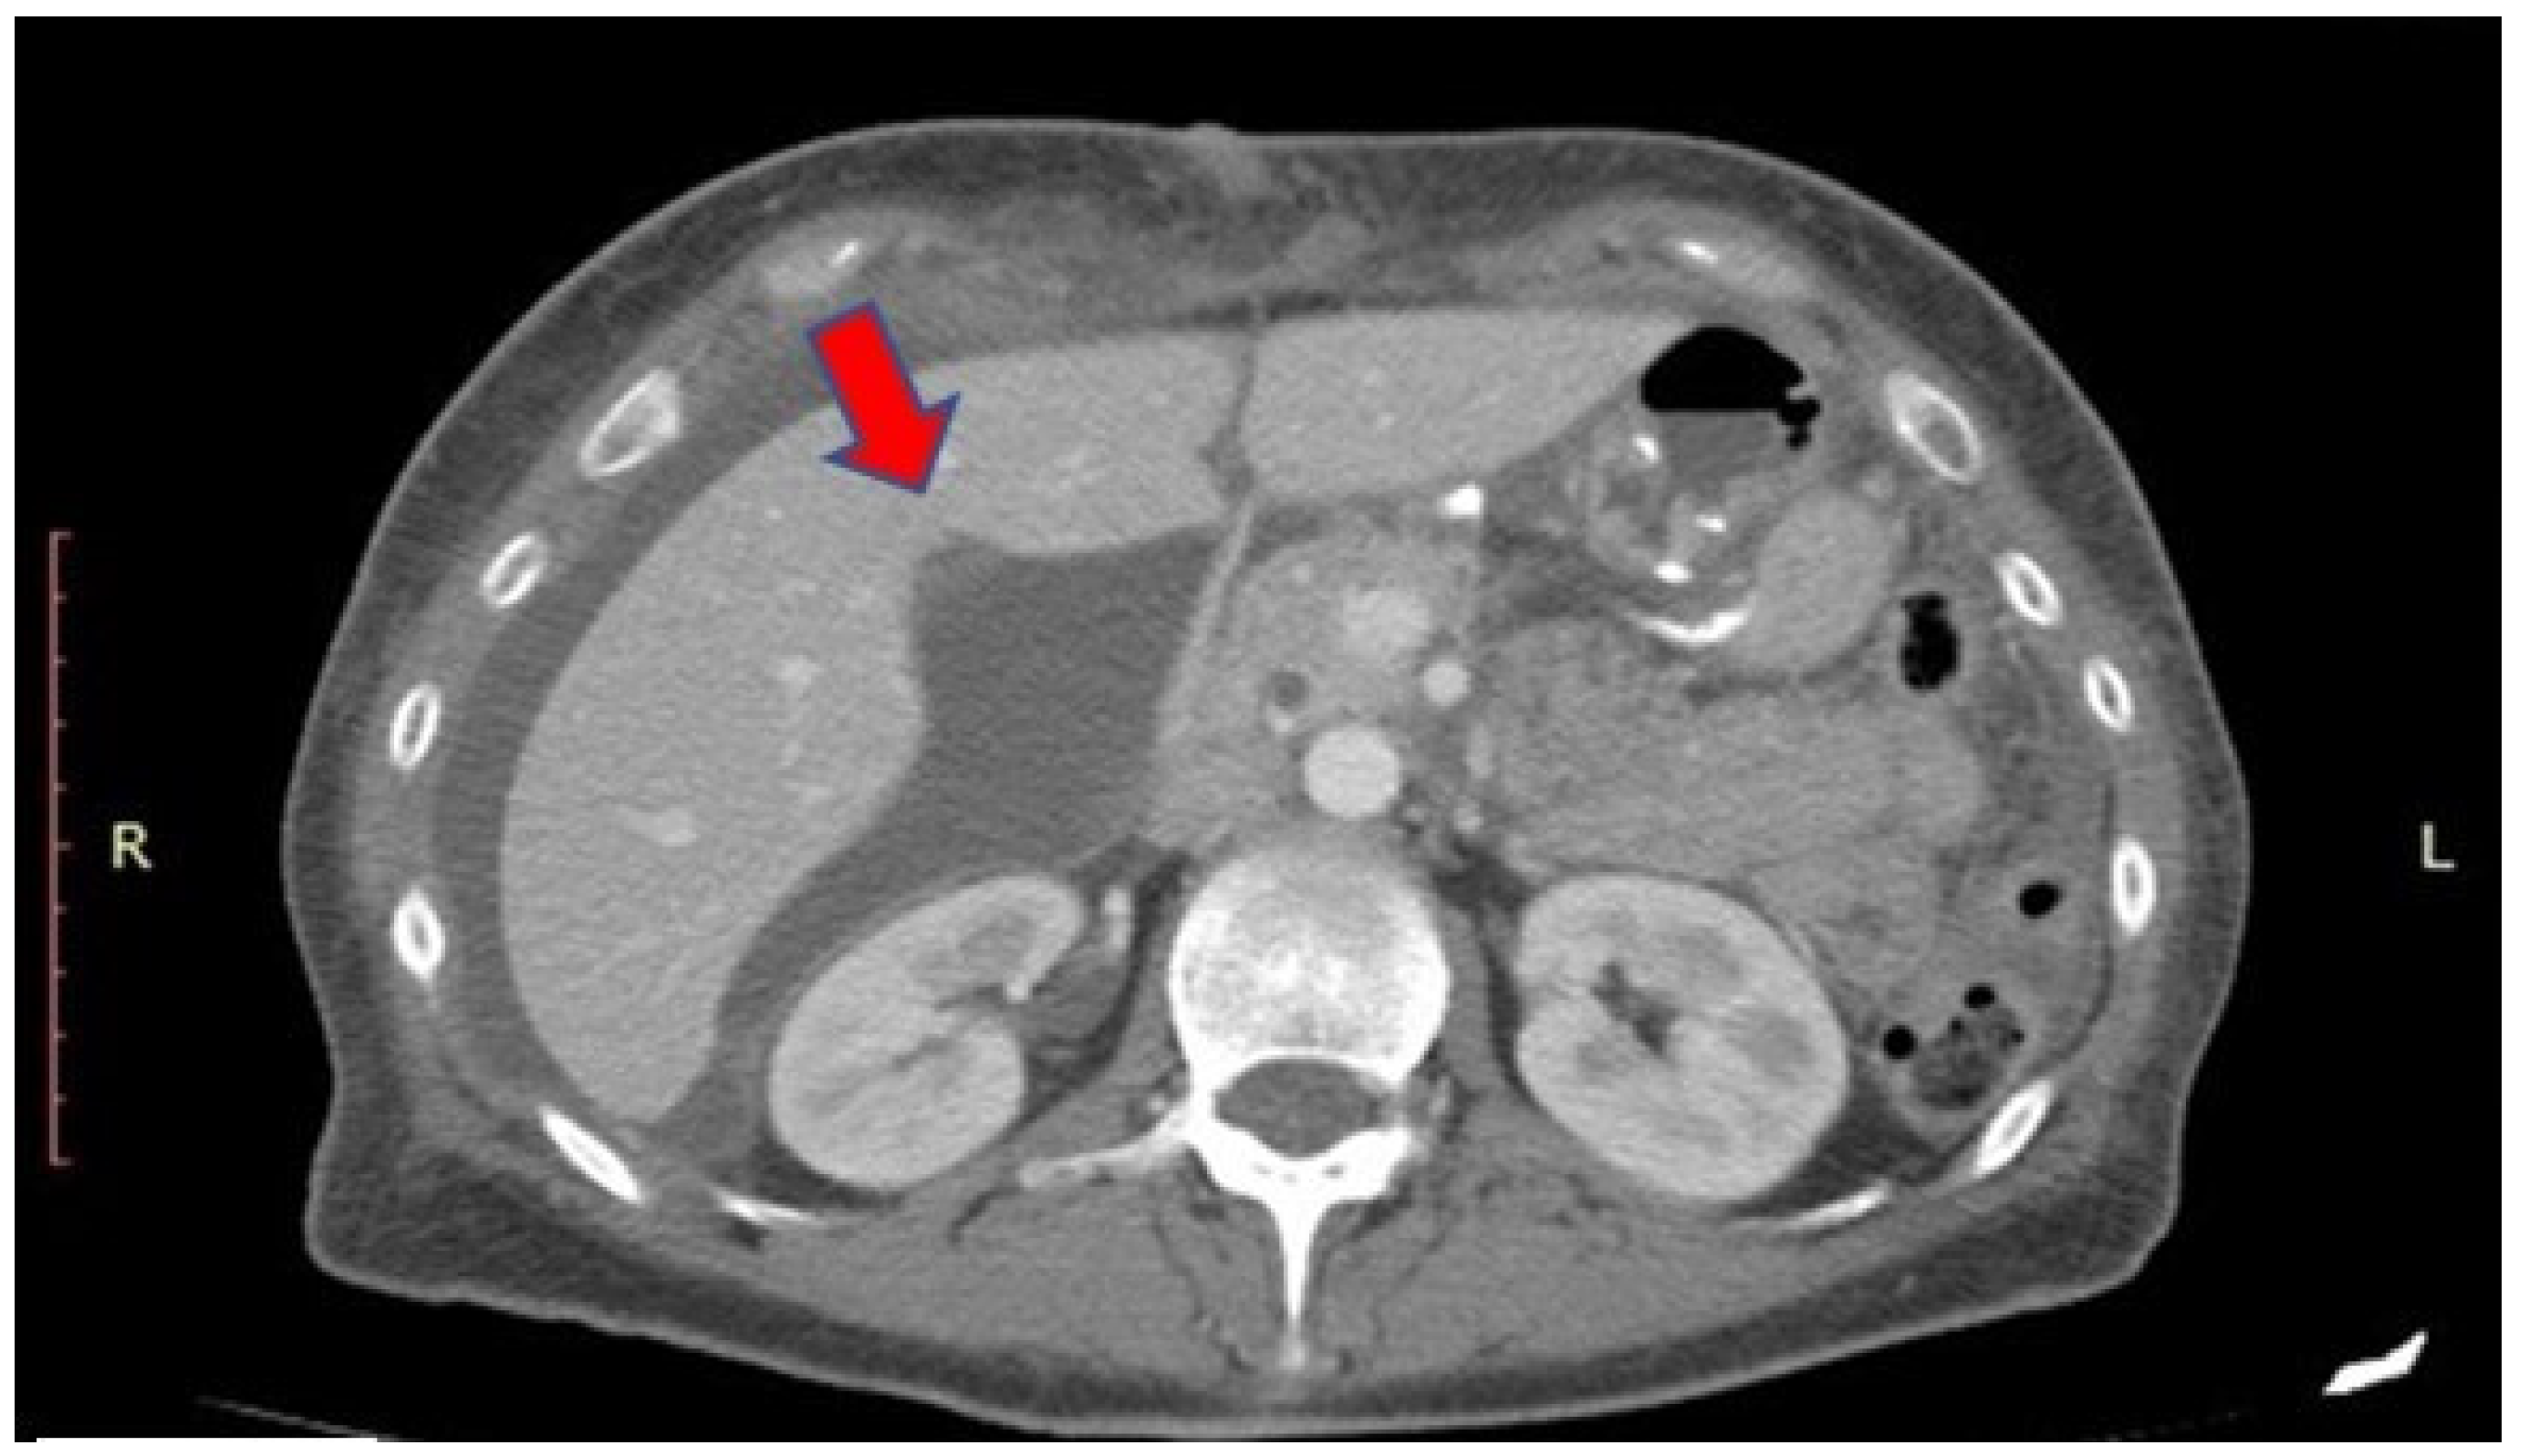

The management of LD leaks mainly depends on the presentation: those cases which are intraoperatively diagnosed are usually clipped during the procedure. However, despite the better view offered by the laparoscope, the intraoperative aspect of the liver bed may appear normal, but a postoperative leak from an LD may occur. The postoperative manifestation of an LD leak is heterogenous and can be treated in several ways according to the clinical manifestation of the patient. In cases where the patient is septic, and a large amount of fluid is seen on imaging (Figure 4) with or without bile duct dilatation, we suggest surgical exploration for abdominal washout. It can be difficult to diagnose the exact location of an LD leak intraoperatively; therefore, we always recommend the assistance of an HPB surgeon and conversion to open surgery in difficult cases. In cases where a small biloma is seen on imaging and the patient is doing well with no signs of sepsis, conservative management can be taken with intravenous antibiotics, ERCP plus or minus stenting and follow-up imaging.

Figure 4.

CT image of a Luschka duct leakage. Red Arrow indicates the bile collection.